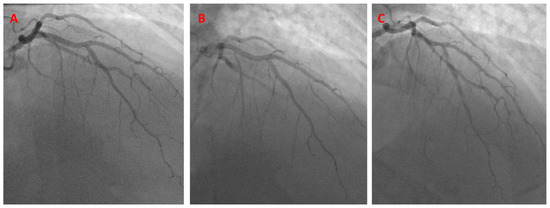

- Case # 3